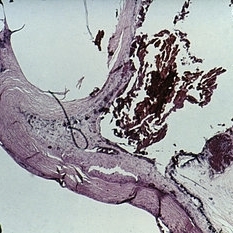

Slide 7-20

Feb 25 2019 by Lancaster Course in Ophthalmology

Carcinoma-in-situ. Although there is a zone of inflammation beneath the tumor, the carcinoma has not invaded beneath its own basement membrane.

Condition/keywords: tumor